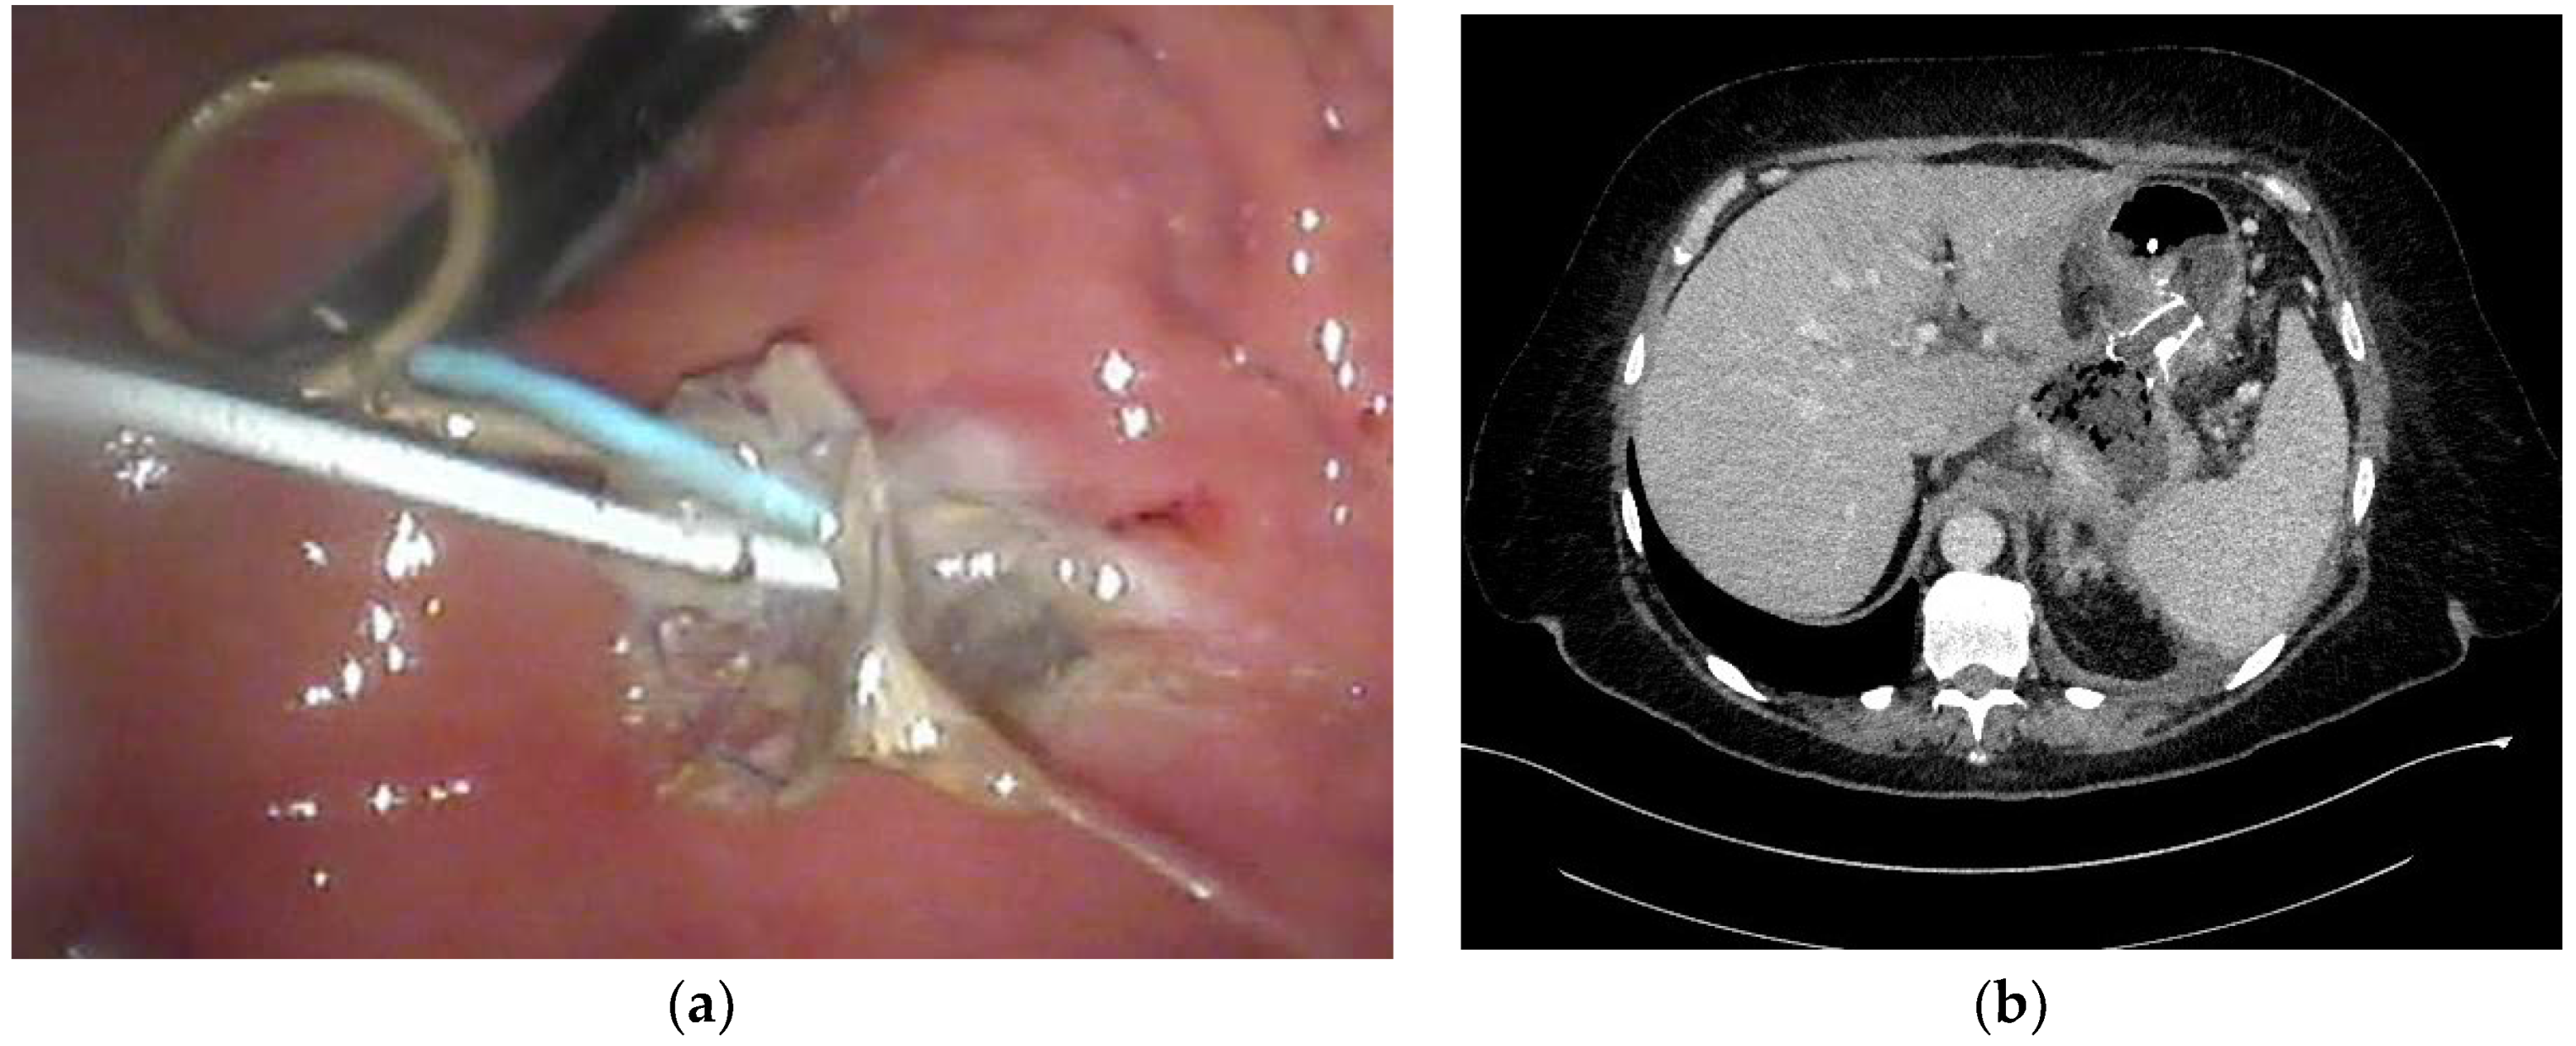

- Smoczyński, M.; Jagielski, M.; Jabłońska, A.; Adrych, K. Endoscopic necrosectomy under fluoroscopic guidance- a single center experience. Wideochir. Inne. Tech. Maloinwazyjne. 2015, 10, 237–243. [Google Scholar] [CrossRef] [PubMed]

- Smoczyński, M.; Jagielski, M.; Siepsiak, M.; Adrych, K. Endoscopic necrosectomy through the major duodenal papilla under fluoroscopy imaging. Arch. Med. Sci. 2018, 14, 470–474. [Google Scholar] [CrossRef] [PubMed]

| Endoscopic necrosectomy under fluoroscopic guidance (endoscopic debridement) | Procedure that enable to remove necrotic tissues from necrotic cavity through transmural fistula under fluoroscopy with use of various types of endoscopic tools. Indication for endoscopic debridement is WOPN containing poorly-liquefied necrotic tissues. |

| Direct endoscopic necrosectomy | Procedure accomplished via insertion of endoscope through the transmural fistula into the lumen of WOPN and direct removal of necrotic tissues under endoscopic view with use of different types of endoscopic tools. Direct endoscopic necrosectomy is usually technically easier to proceed during transmural drainage with use of SEMSs. Indications for direct endoscopic necrosectomy are extensive WOPN containing poorly-liquefied necrotic tissues without clinical improvement despite active transmural drainage. |